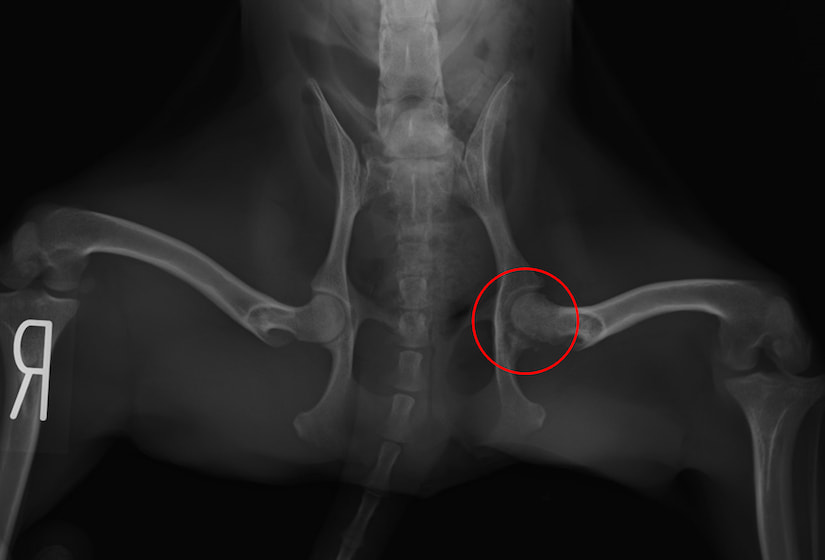

大体骨頭壊死症(レッグ・ペルテス病)(2024/07/09)

大腿骨の先端(大腿骨頭)への血液の供給が上手くいかない事で変形や壊死を起こしてしまう股関節の疾患です。主に4ヶ月齢〜1歳未満の、成長期の小型犬で発症することが多いと言われています。後ろ足を庇うように歩いたり、痛みで足を挙げるようになったり、その結果として筋肉が痩せ細ったりして、上手く歩けなくなってしまいます。触診やレントゲン検査などを用いて診断し、多くの場合は大腿骨頭を切除する外科的な治療を行います。少しでもワンちゃんの歩き方に違和感を感じた場合は、お早めにご相談下さい。